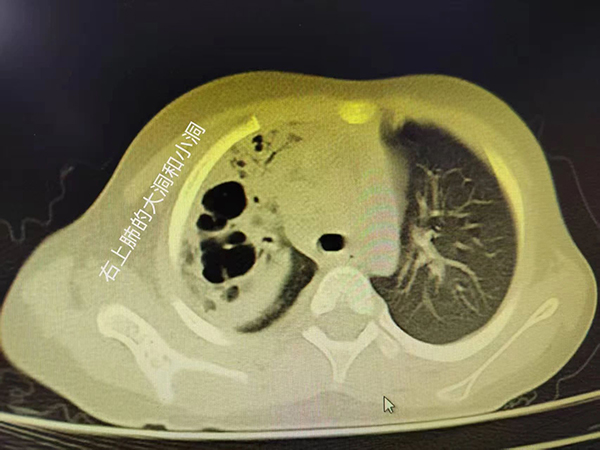

入院后的胸部CT证实了我们的判断,病情不容乐观!热程已拖到10天,秉承着重症感染抗炎要重拳出击的原则,我们马上予以强有力的联合抗炎治疗,力求最快控制感染,并迅速安排了支气管镜术,在短时间内取得了病原结果,竟是“肺炎链球菌”这个经典的家伙!它的威力可不容小觑,只不过几天,小朋友的肺子就被啃成了“筛子”!

早期可见肺纹理增强或局限于一个节段的浅薄阴影,之后可能会出现大片状阴影,占全肺叶或一个节段。少数患者出现肺大疱或胸腔积液。个别肺炎链球菌肺炎出现化脓性并发症,可出现肺实变区的坏死病灶(看起来像是肺子成了筛网),或出现支气管肺胸膜瘘或大小不等的脓肿等。